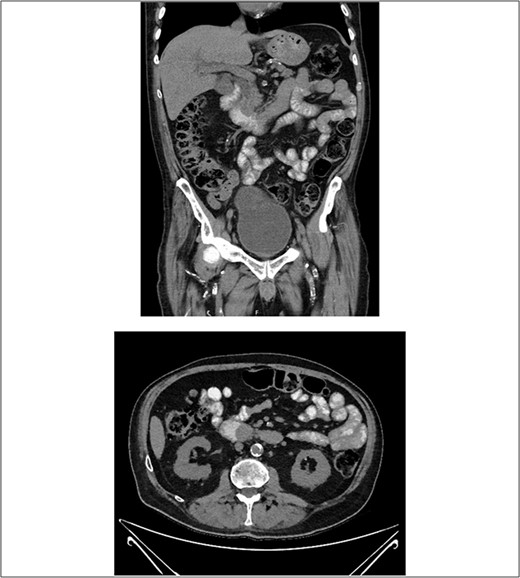

After consultation with our Hepatobiliary service, the consensus was for the patient to undergo an urgent ERCP. Intraoperatively, a duodenoscope was introduced through the mouth and was advanced to the duodenum at the ampulla of Vater. The major papillae were bulging and a malignant appearing infiltrative mass was visualized. A tapered tip cannula was inserted through the ampulla and contrast was injected, revealing a patent PD and a single 18-mm long stenosis of the distal third of the CBD with significant dilatation of the proximal CBD and intrahepatic ducts (Fig. 2). A 10Fr 7-cm transpapillary plastic stent was inserted with a single internal flap, 5.5 cm, into the CBD. The biliary pancreatic junction was biopsied with cold forceps for histology. Cholangiopancreatography revealed the stent was in good position with good flow of contrast into the duodenum beyond the filling defect (Fig. 3).

(A) and (B) malignant appearing soft tissue infiltrative mass within the ampulla of Vater seen on ERCP; (C) cholangiopancreatography showing stenosed distal third of the common bile duct along with a patent pancreatic duct.